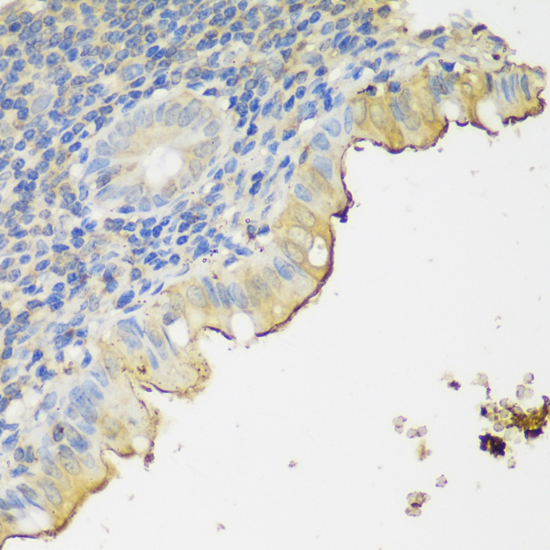

DescriptionCLN5 Polyclonal Antibody. Unconjugated. Raised in: Rabbit.

ApplicationWB, IHC; Recommended dilution: WB 1:500 - 1:2000, IHC 1:50 - 1:200